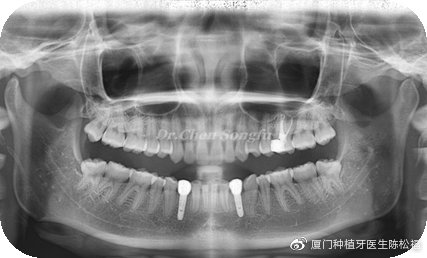

2、全口正畸治疗推出,33,43的种植修复间隙,调整覆合

3、十二个月后行33,43种植

4、十五个月后完成最终修复

治疗效果:前后对比图片

1、正畸治疗开辟了合适的修复空间的同时,纠正了前牙不良的覆合关系。

2、良好的种植设计与种植修复恢复了可靠的修复效果。